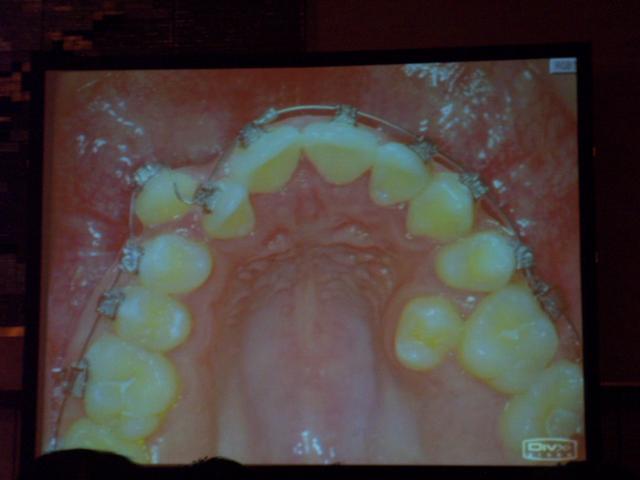

デーモンシステムによる歯の動きの変化